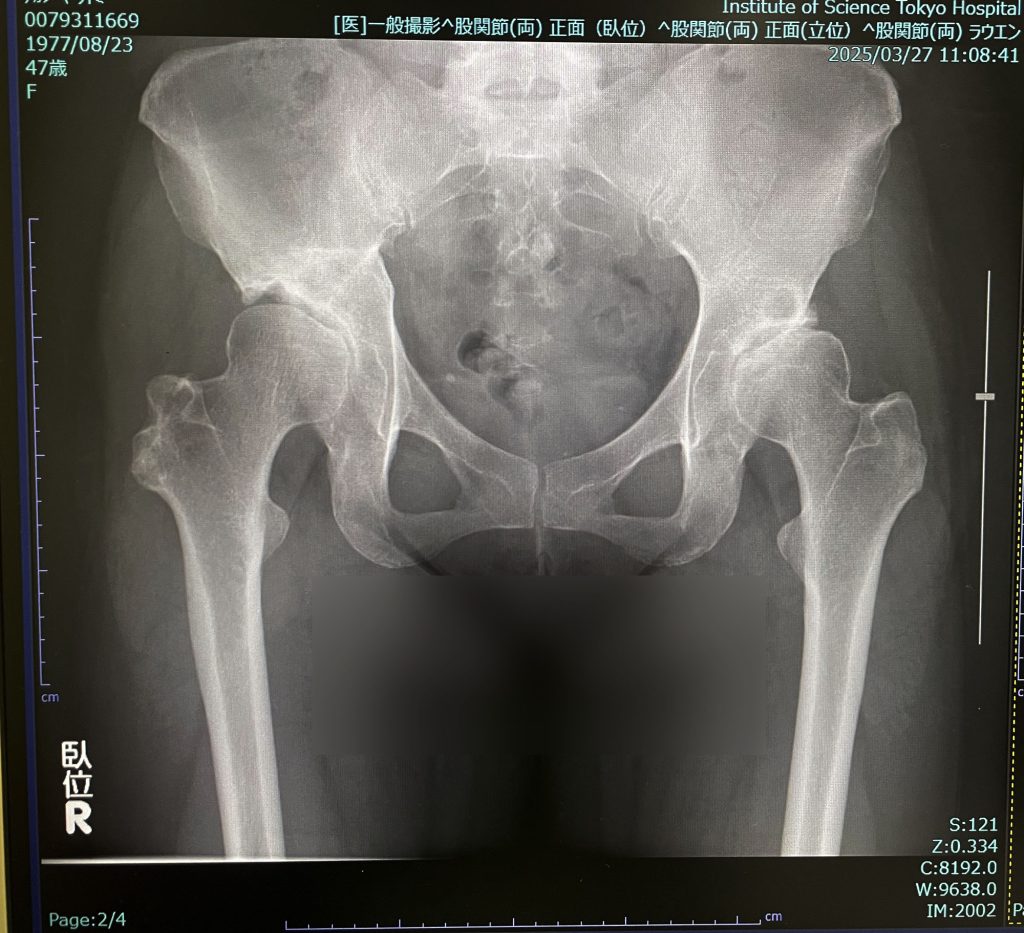

今回のレントゲン

2年前との比較。

・2年前と比較してそんなに大きく変わっている様子はない。多少隙間が狭くなった感じはある